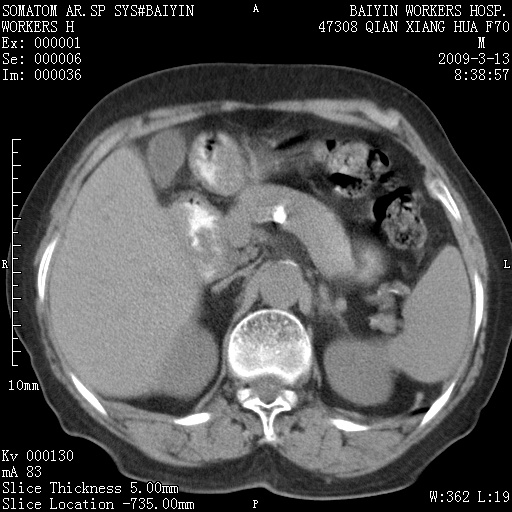

标题: CT18651:左肾上腺占位,请会诊!

女,70岁,体检发现。

左肾上腺腺瘤

左侧肾上腺结节状软组织密度影;考虑肿瘤(肾上腺腺瘤?转移瘤?)。

左侧肾上腺占位,腺瘤?不除外转移。

左侧肾上腺占位,腺瘤可能。

左侧肾上腺占位,考虑腺瘤可能。